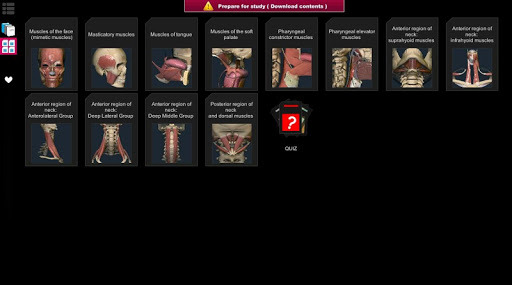

A true and totally 3D app for studying human anatomy, built on an advanced interactive 3D touch interface.

★ 3D location quizzes to test your knowledge

★ Muscles